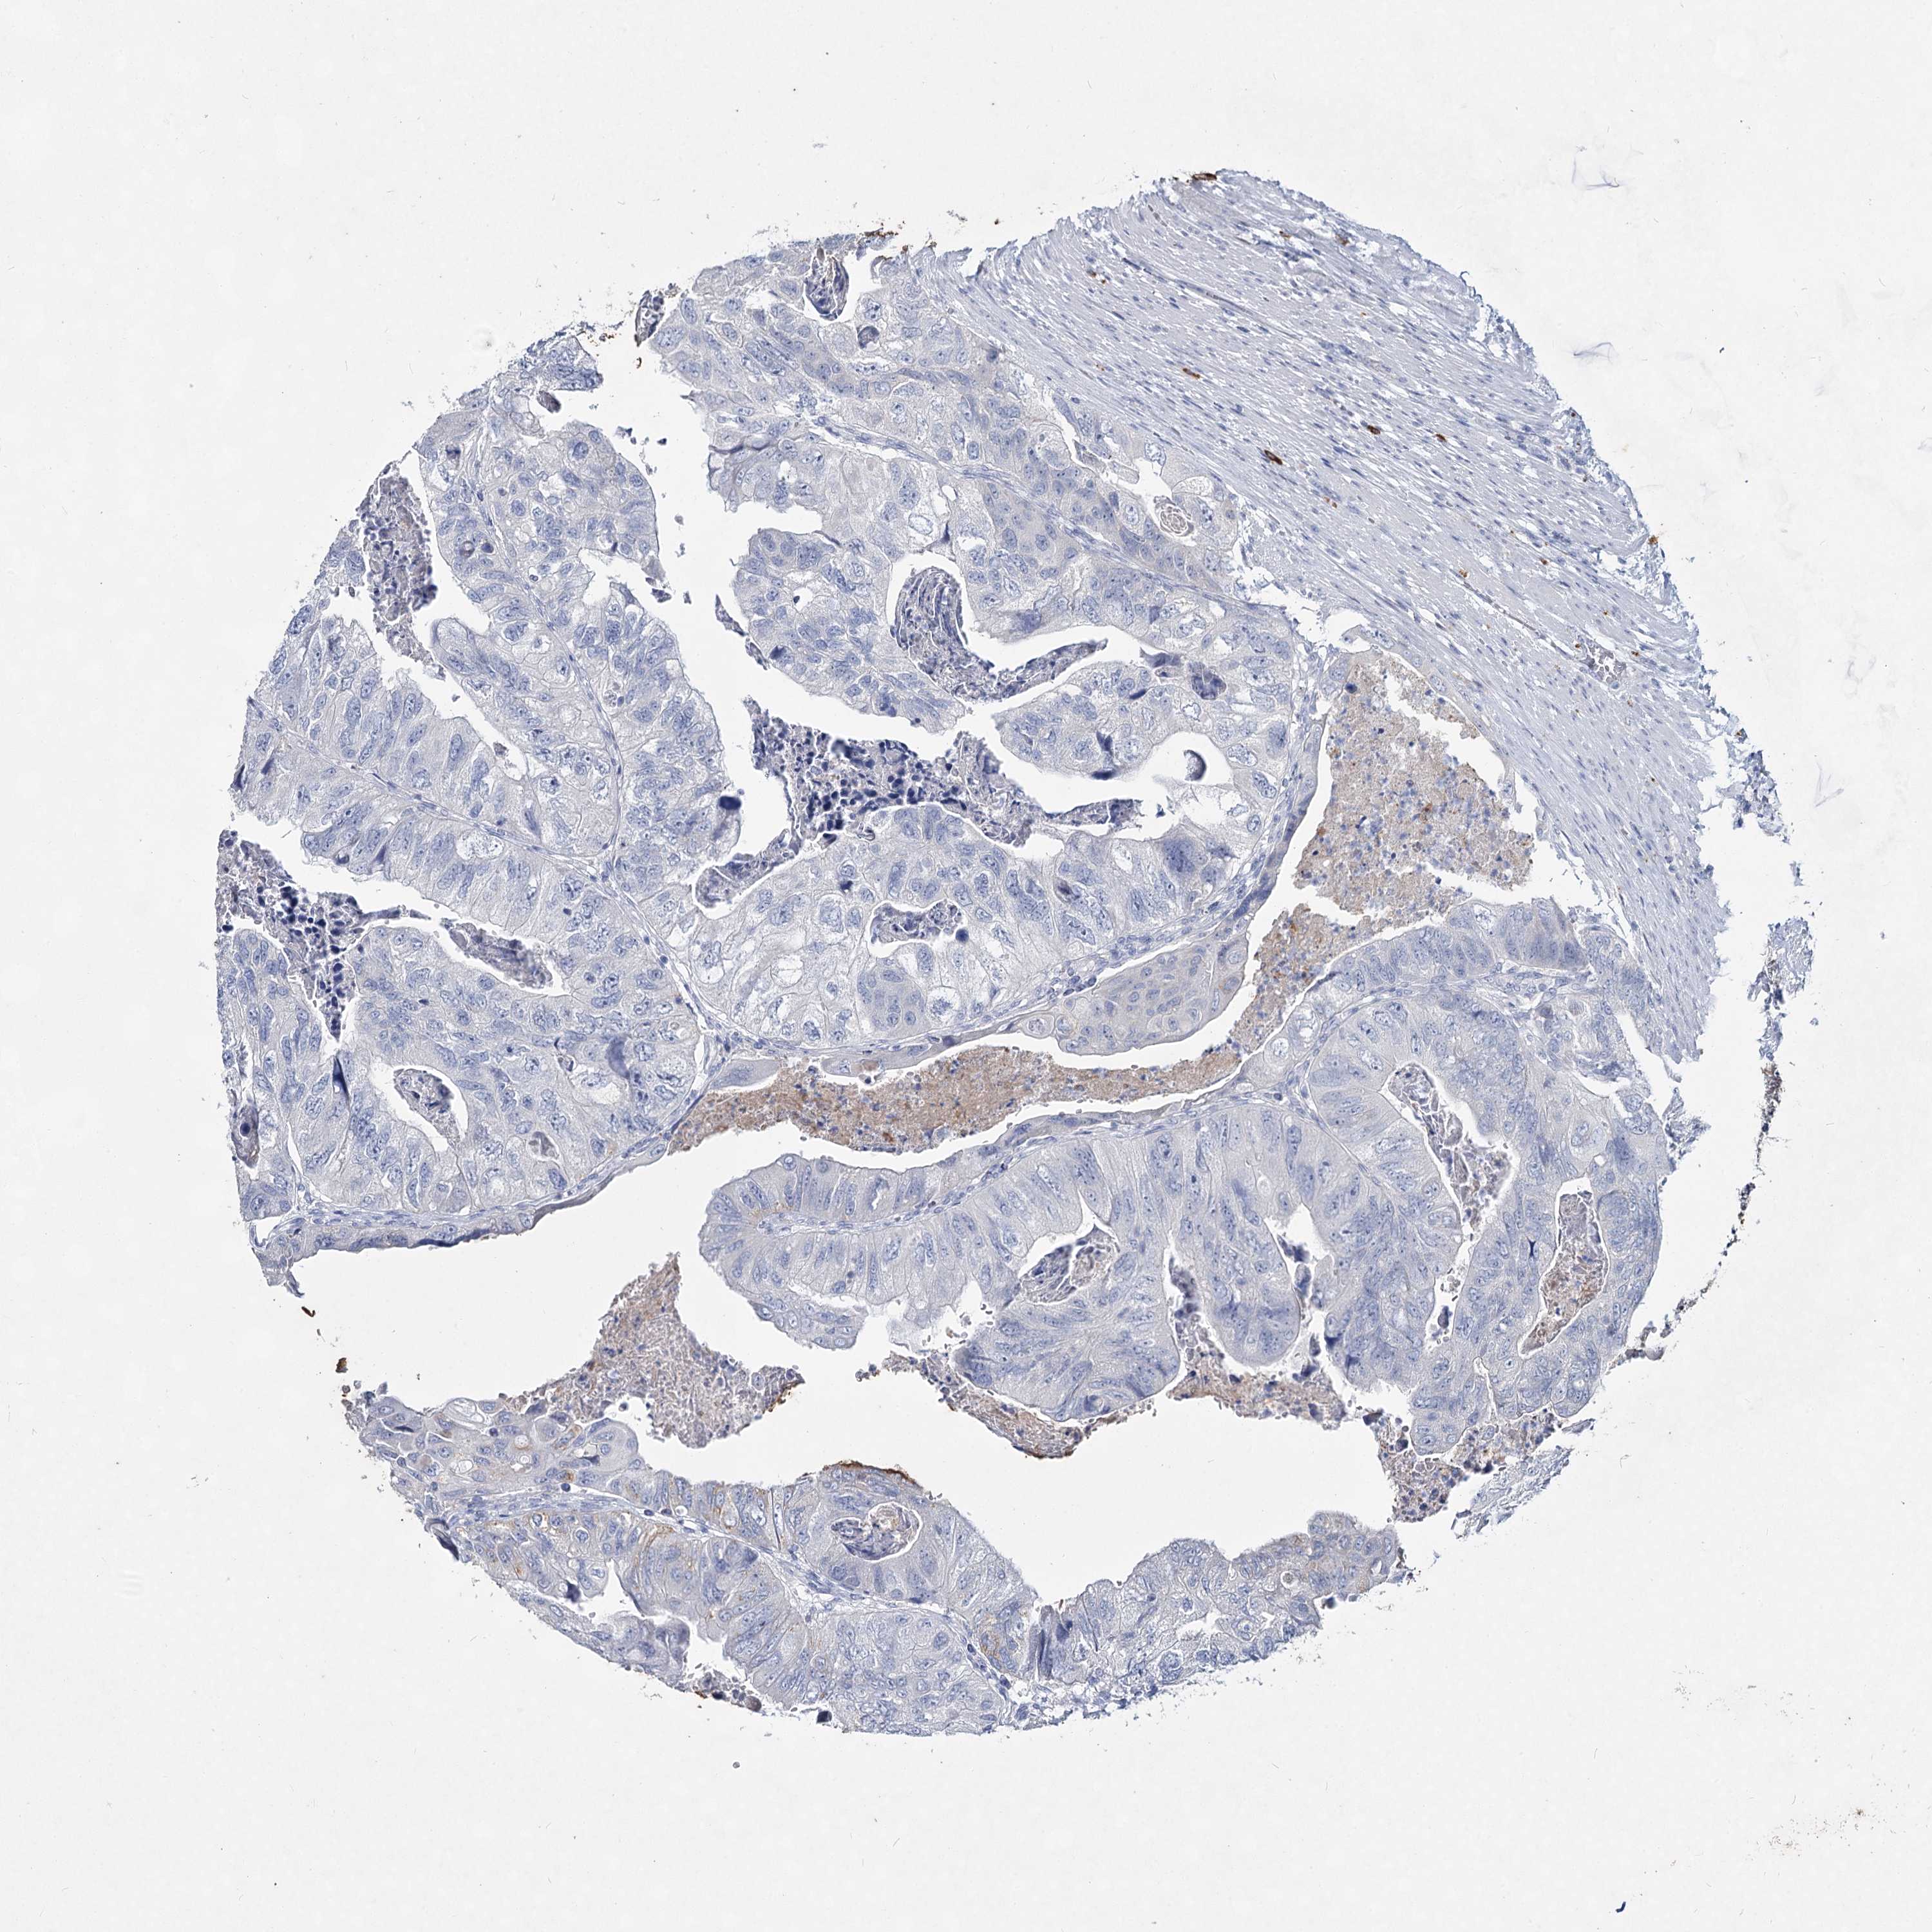

CANCER COLORECTAL CANCER Show tissue menu

Colorectal cancer

Human cancer

Colon adenocarcinoma